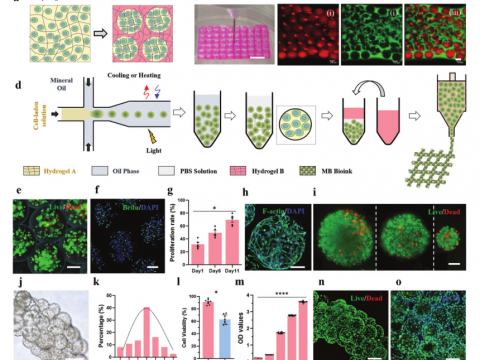

- 中国团队「六轴细胞3D打印机」登顶刊!心肌组织体外存活超6个月

- 6自由度的全新机器人手臂,协同3D打印铸造可以跳动的心肌组织

- 清华大学张婷、熊卓团队:用于3D打印的载细胞微凝胶基双相生物墨水